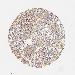

LUNG SQUAMOUS CELL CARCINOMA (TCGA) - Interactive survival scatter ploti

The Survival Scatter plot shows the clinical status (i.e. dead or alive) for all individuals in the patient cohort, based on the same data that underlies the corresponding Kaplan-Meier plots. Patients that are alive at last time for follow-up are shown in blue and patients who have died during the study are shown in red.

The x-axis shows the expression levels (FPKM) of the investigated gene in the tumor tissue at the time of diagnosis. The y-axis shows the follow-up time after diagnosis (years). Both axes are complimented with kernel density curves demonstrating the data density over the axes. The top density plot shows the expression levels (FPKM) distribution among dead (red) and alive patients (blue). The right density plot shows the data density of the survived years of dead patients with high and low expression levels respectively, stratified using the cutoff indicated by the vertical dashed line through the Survival Scatter plot. This cutoff is automatically defined based on the FPKM cutoff that minimizes the p-score. The cutoff can be changed by dragging the vertical line or by entering a cutoff value in the square labeled "Current cut-off".

Under the Survival Scatter plot the p-score landscape (black curve; left axis) is shown together with dead median separation (red curve; right axis). Dead median separation is the difference in median mRNA expression between patients who have died with high and low expression, respectively. It is calculated as follows: median FPKM expression of dead patients with high expression - median FPKM expression of dead patients with low expression. This is intended to aid the user in visually exploring custom cutoffs and the associated p-scores and dead median separation.

Individual patient data is displayed and can be filtered by clicking on one or more of the category buttons on the top of the page. Categories describing expression level and patient information include: high, low, alive, dead, female, male and tumor stages. The scale of the x-axis can be toggled between linear and log-scale by clicking on the "x log" button. Mouse-over function shows TCGA ID, patient information and mRNA expression (FPKM) for each patient.

& Survival analysisi

Kaplan-Meier plots summarize results from analysis of correlation between mRNA expression level and patient survival. Patients were divided based on level of expression into one of the two groups "low" (under cut off) or "high" (over cut off). X-axis shows time for survival (years) and y-axis shows the probability of survival, where 1.0 corresponds to 100 percent.

LRG1 is not prognostic in Lung Squamous Cell Carcinoma (TCGA)

: 7.43